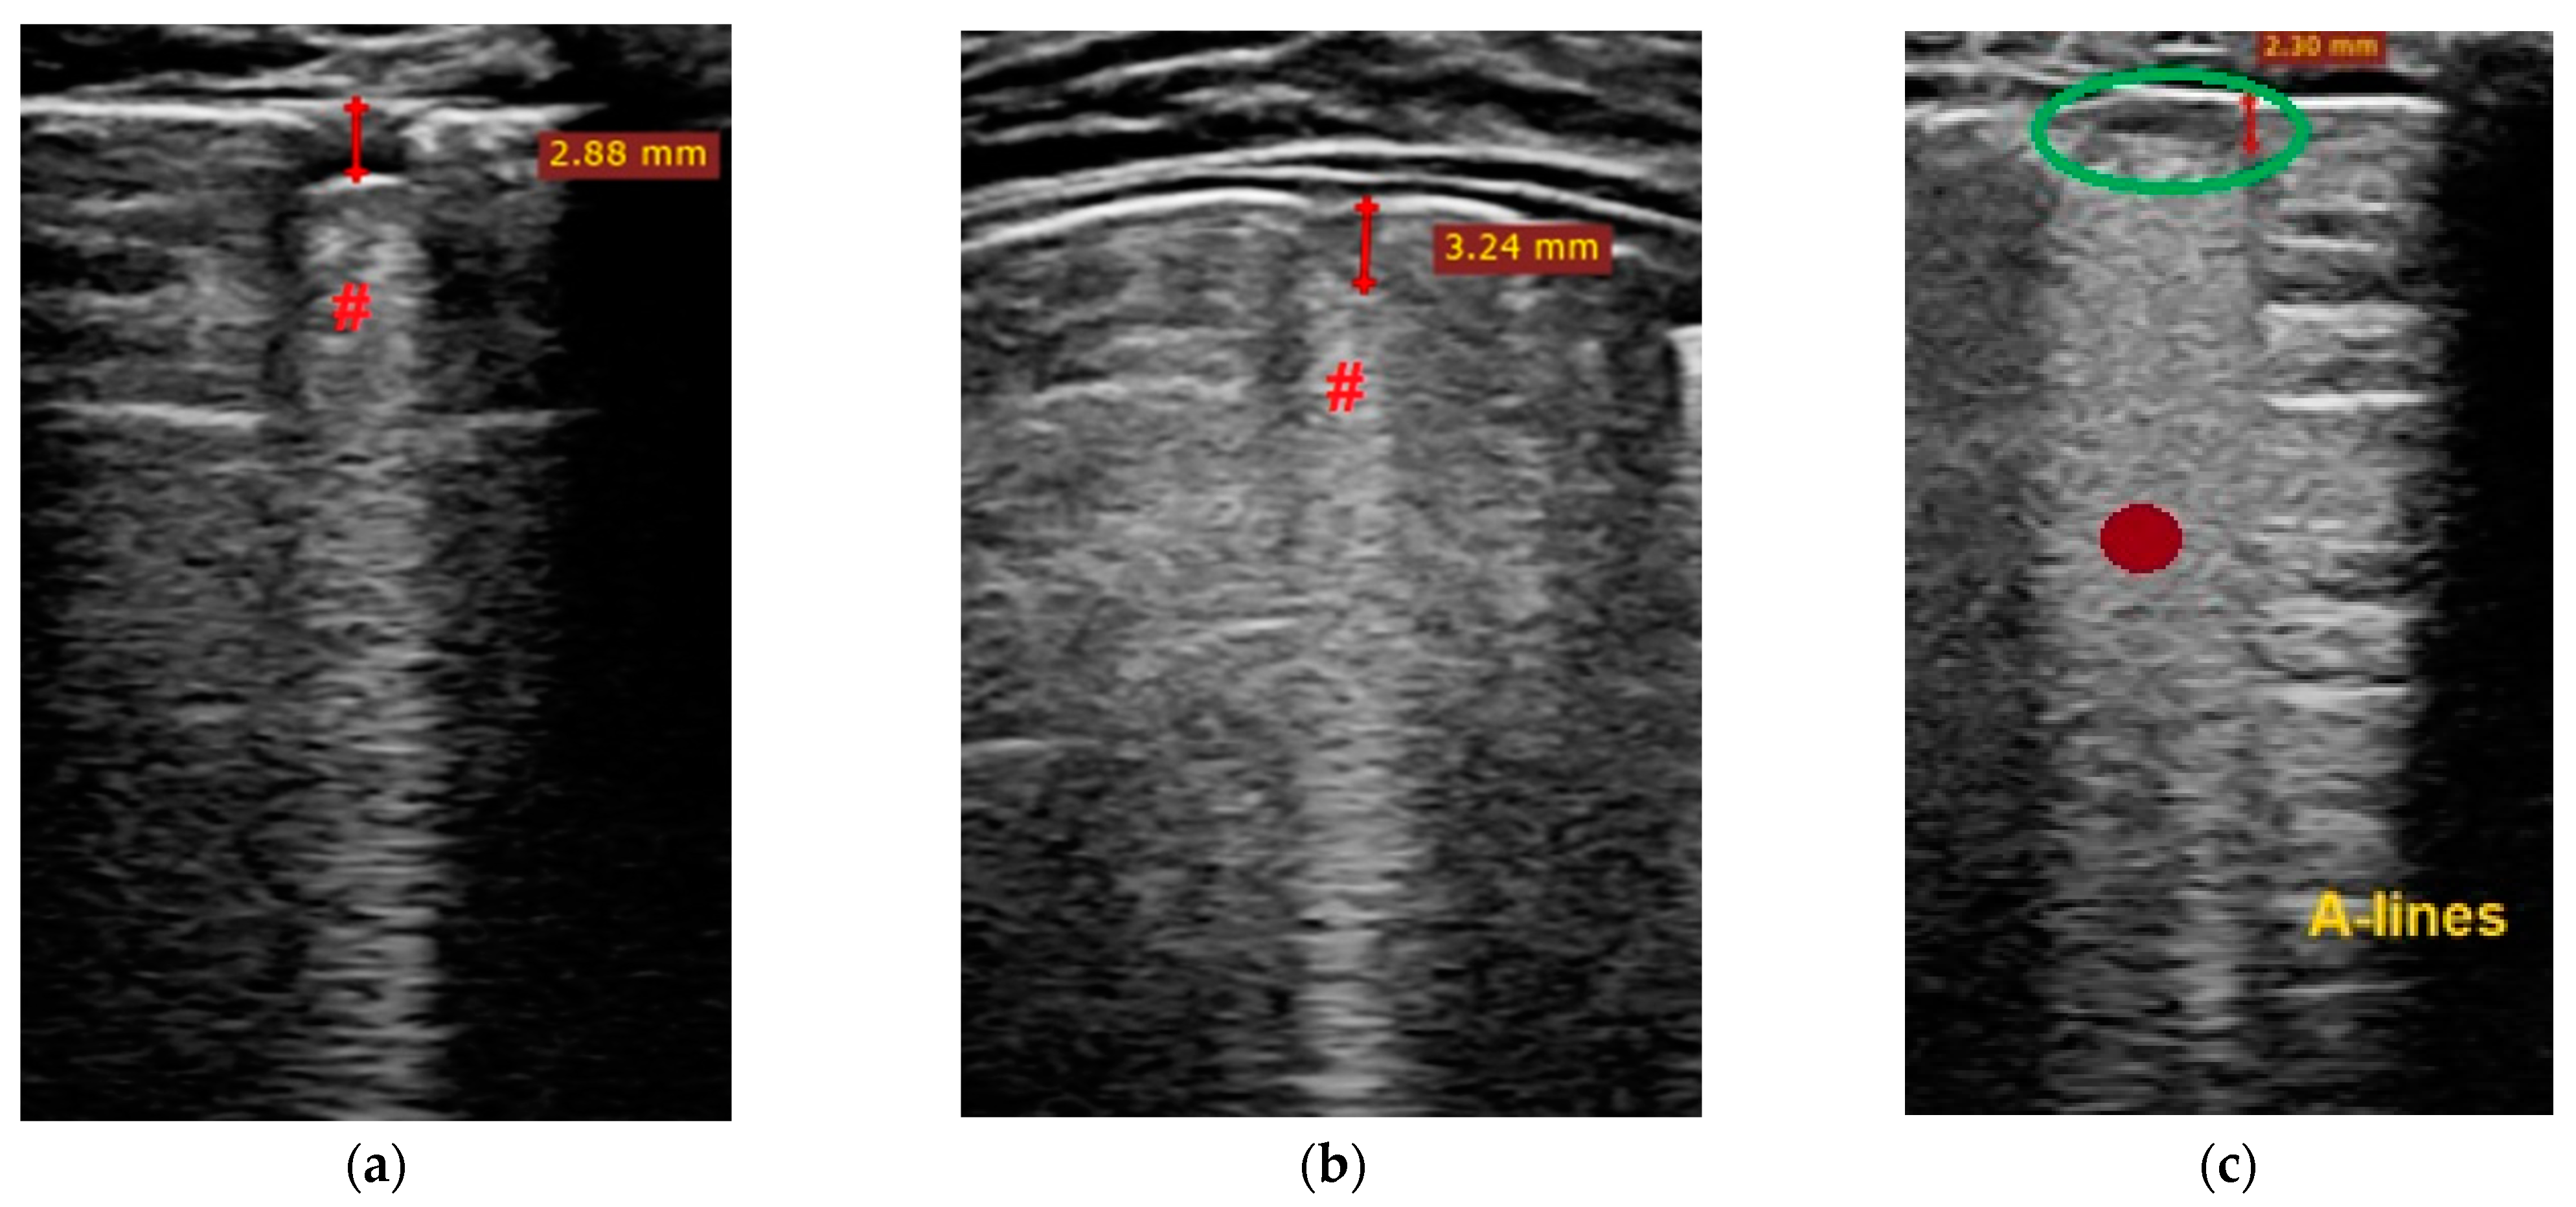

- Transverse physiologic A-lines that depict healthy parenchyma;

- Isolated/sparse vertical B-lines are equivalent to interstitial edema;

- Confluent vertical B-lines correspond to alveolar edema;

- Subpleural/peripheral consolidations;

| Normal/physiological A-lines | More than 2 B-lines (sparse B-lines) with associated pleural abnormalities | Coalescent or confluent B-lines | Large peripheral consolidation (wider than 1 cm) in association or not with air bronchogram |

| One or two B-lines per intercostal space | ‘White-lung’ aspect or small peripheral consolidation (smaller than 1 cm) |